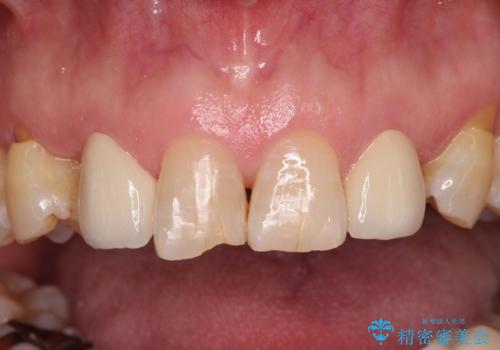

- 乳歯や矮小歯が多くある前歯部の審美障害が気にして来院された患者様です。

上顎の矮小歯は隙間が多く、歯軸の傾斜も大きかったため、部分矯正により補綴治療前に歯の位置を整えることとしました。

前歯部はディープバイトという、上顎前歯が下顎前歯に深く覆い被さる咬合であったので、理想的には全顎矯正が必要となりますが、今回は患者希望により前歯部のみの部分矯正で対応しました。そのため下顎犬歯の神経を取り除くことになってしまったのは心残りであります。